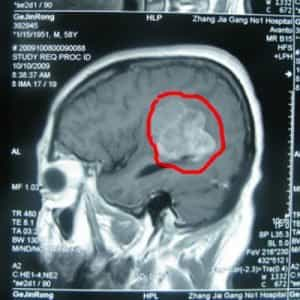

تم إدخال المريض جينغونغ غي، وهو مريض ذكر يبلغ من العمر 59 عامًا من الصين، إلى مستشفى بكين بوهوا الدولي (BPIH) في الصين في 20 أكتوبر 2009، مصابًا بورم سحائي غير نمطي في منطقة مثلثة.

قبل ستة عشر شهرًا من دخوله المستشفى بسبب ورم سحائي غير نمطي في المنطقة المثلثية اليسرى، بدأ السيد جي يشعر بضعف في مرونة ساقه اليمنى، وكأنه يعاني من ضعف في حركتها. لم يسعَ للعلاج فورًا. مرت ستة أشهر، وتفاقمت الأعراض تدريجيًا، مما أثر على مشيته، وكان لصعوبة تحريك ساقه اليمنى أثر سلبي واضح على حياته. ذهب إلى مستشفى محلي وأجرى تصويرًا بالرنين المغناطيسي للدماغ، والذي أظهر وجود ورم في المنطقة المثلثية من البطين الجانبي الأيسر. نُصِحَ بالتدخل الجراحي. رغبةً منه في الخضوع لجراحة الأعصاب لعلاج هذا الورم السحائي غير النمطي، تم إدخال المريض جينرونغ جي إلى مستشفى بكين الدولي للأمراض النفسية.

فحص بالأشعة قبل الجراحة